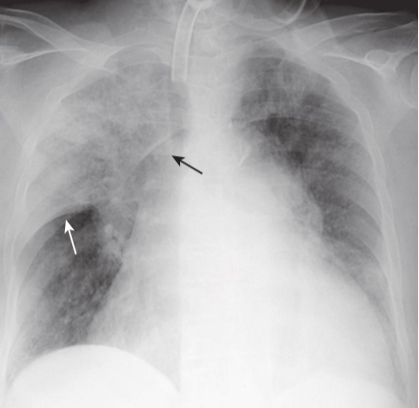

Large left pleural effusion.

The left hemithorax is completely opacified, and there is a shift of the mobile mediastinal structures, such as the trachea (solid black arrow) and the heart(dotted black arrow), away from the side of opacification. This is characteristic of a large pleural effusion, which can act like a mass. In most adults, it requires about 2 L of fluid to fill or almost fill the entire hemithorax such as shown here.